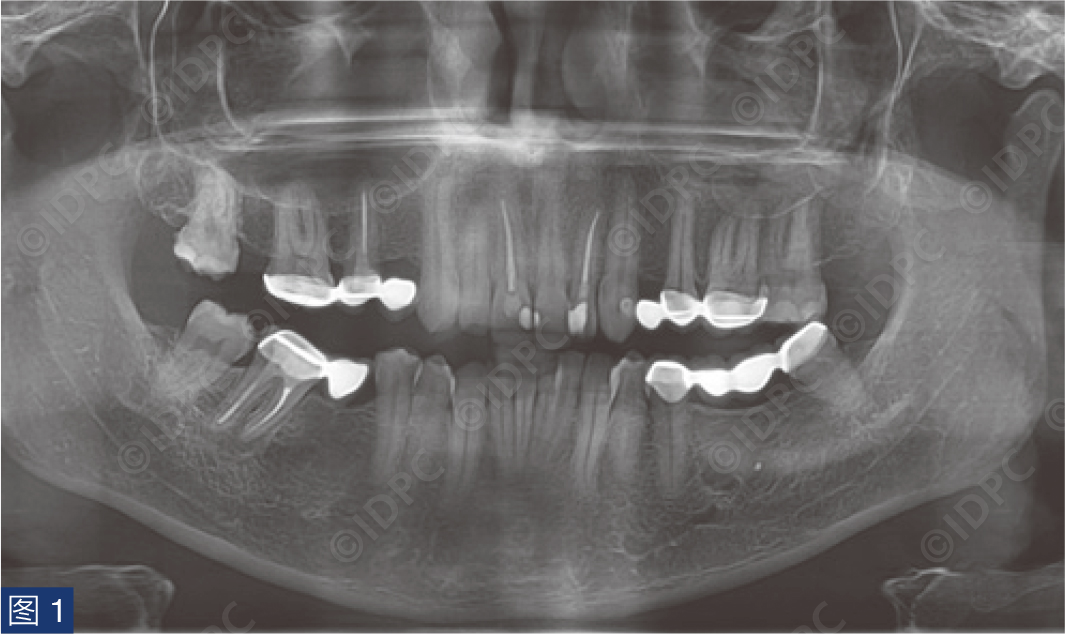

在exocad软件(exocad公司)上进行全数字化修复流程设计,在copaSKY uni.fit钛基底(bredent medical公司)上制作完成螺丝固位氧化锆混合陶瓷一体冠。种植位点显示出足够的颊侧软组织厚度(图12a)及良好的牙龈轮廓(图12b)。取下个性化愈合基台后,种植体周围软组织健康(图13、14),此外,取下后立即进行术前口内扫描以记录软组织轮廓。随后放置扫描体并进行数字印模以记录种植体位置(图15)。同时扫描对颌牙弓及咬合信息。获得的STL文件以数字方式发送至技工室。技工室在钛基底上完成聚甲基丙烯酸甲酯(PMMA)材料的试戴牙冠,以检查邻接和边缘密合情况,同时调整咬合(图16、17)。一旦完成所有调整,进行重新扫描。最终在钛基底上完成螺丝固位的全结构氧化锆混合陶瓷修复体,与牙龈接触的修复体表面高度抛光(图18),并以25 Ncm戴入口内。修复体实现了出色的颜色匹配及临床结果(图19)。螺丝孔用聚四氟乙烯填塞并用树脂材料密封(图20)。术后对照X线片显示修复体正确就位(图21)。六个月复查,增加的软组织轮廓清晰可见,牙槽骨水平保持稳定(图22-24)。

图21:最终修复体戴入后X线片。